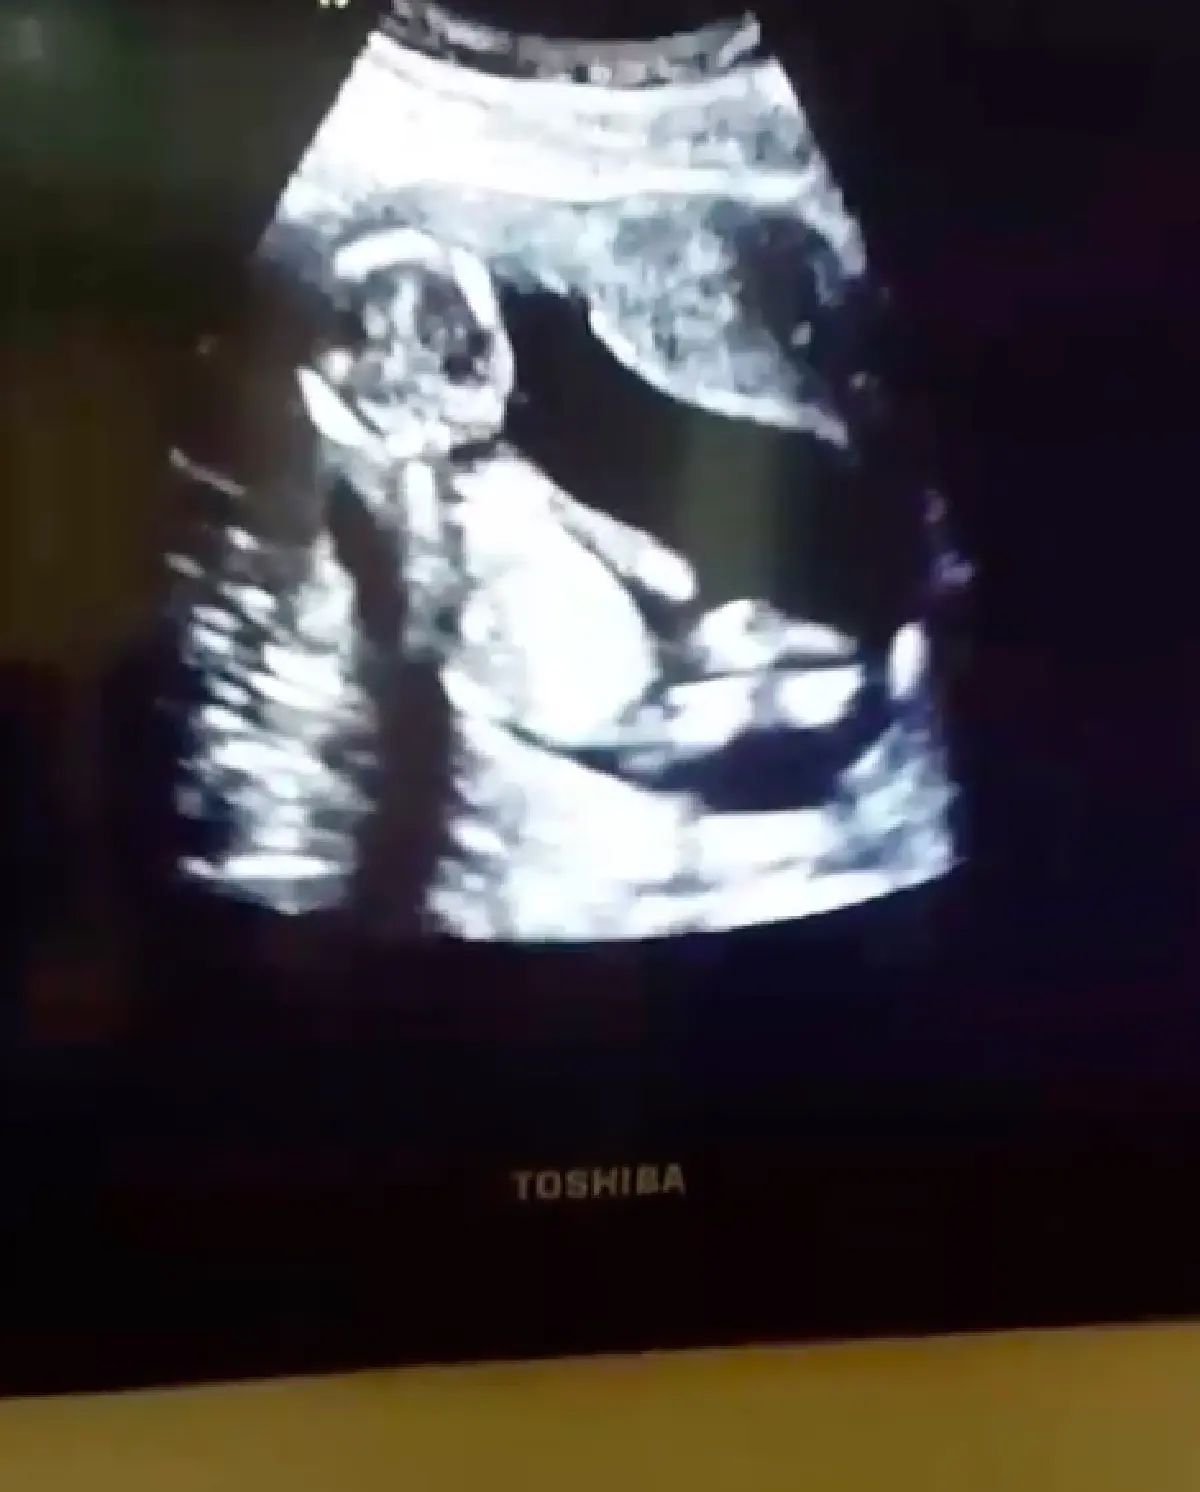

ดั้งโด่งเหมือนพ่อ! "ศรราม" โชว์คลิปอัลตร้าซาวด์ลูกสาว "น้องวีจิ”

"ศรราม" โชว์คลิปอัลตร้าซาวด์ลูกสาว "น้องวีจิ” ขายาว จมูกโด่ง ฉายแววสวยตั้งแต่ในท้อง

ล่าสุด “ศรราม” ก็ได้ออกมาเผยคลิปอัลตร้าซาวด์ลูกสาว ฟังเสียงหัวใจ และดูการเติบโต ขนาดของลูกสาว ดูคุณพ่อก็จะแฮปปี้สุดๆ อีกทั้ง "น้องวีจิ” ก็ดั้งโด่งเหมือนคุณพ่ออีกด้วย